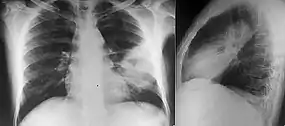

Diabetes mellitus is one of the most important risk factors in developing melioidosis. The disease should be considered in anyone who has spent time in endemic areas who develops a fever, pneumonia, or abscesses in their liver, spleen, prostate, or parotid gland.[1] The clinical manifestation of the disease can range from simple skin changes such as abscesses or ulcerations to severe organ problems.[7] In northern Australia, 60% of the infected children presented with only skin lesions, while 20% presented with pneumonia.[2] The commonest organs affected are liver, spleen, lungs, prostate, and kidneys. Among the most common features are bacteremia (in 40 to 60% of cases), pneumonia (50%), and septic shock (20%).[1] People with only pneumonia may have a prominent cough with sputum and shortness of breath. However, those with septic shock together with pneumonia may have minimal coughing.[3] Results of a chest X-ray can range from diffuse nodular infiltrates in those with septic shock to progressive consolidation located most commonly in the upper lobes for those with pneumonia only. Pleural effusionğ and empyema are more common for melioidosis affecting lower lobes of the lungs.[3] In 10% of cases, people develop secondary pneumonia caused by other bacteria after the primary infection.[2]

Various imaging modalities can also help with the diagnosis of melioidosis. In acute melioidosis with the spreading of the bacteria through the bloodstream, the chest X-ray shows multifocal nodular lesions. It may also show merging nodules or cavitations. For those with acute melioidosis without the spread to the bloodstream, chest x-ray most commonly shows upper lobe consolidation or cavitations.[8] In chronic melioidosis, the slowly progressing of upper lobe consolidation of the lungs resembles tuberculosis.[8] For abscesses located in other parts of the body apart from the lungs, especially in the liver and spleen, CT scan has higher sensitivity when compared with an ultrasound scan. In liver and splenic abscesses, an ultrasound scan shows "target-like" lesions while CT scan shows "honeycomb sign" (abscess with loculations separated by thin septa) in liver abscesses.[8] For melioidosis involving the brain, MRI have higher sensitivity than a CT scan in diagnosing the lesion. MRI shows ring-enhancing lesions for brain melioidosis.[8]